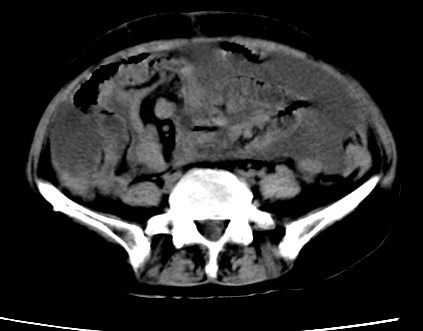

标题: CT23975:女61岁,腹部不适,明显消瘦 [打印本页]

标题: CT23975:女61岁,腹部不适,明显消瘦

既往5年前卵巢癌行子宫及附件切除,右乳癌术后一年,考虑腹膜转移?

大量腹水,考虑腹膜转移。肝脏低密度灶。1囊肿,2转移。

1)结合病史,考虑腹膜及网膜转移瘤。2)肝脏多发性低密度灶,不排除转移瘤。3)大量腹水。

考虑卵巢癌行子宫术后复发,并肝、腹腔 、大网膜转移可能性大。

大量腹水。